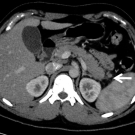

A 70-year-old woman presented to the emergency department with right lower quadrant abdominal pain, nausea, and vomiting.